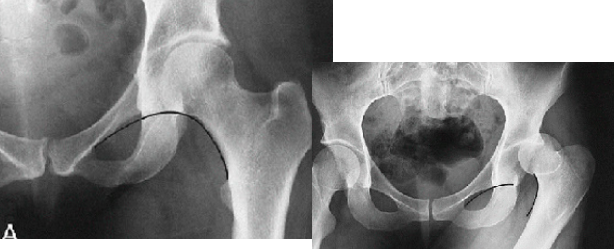

Q what is the name of this measurement? and what is the average + range?

A: Teardrop Distance

assesses the distance from the femoral head to the pelvic teardrop. The average is 9 mm, with a range of 6-11 mm.

A: Hip Joint Space Width

assesses the width of the hip joint space. The average is 4 mm, with ranges of 3-6 mm (superior), 3-7 mm (axial), and 4-13 mm (medial). The average for the medial joint space (teardrop distance) is 8 mm.

A: Shenton's Line

assesses the alignment of the femoral neck and superior pubic ramus. congruency is normal

A: Iliofemoral Line

assesses the alignment of the ilium, hip joint, and femoral neck. No average or range is specified.